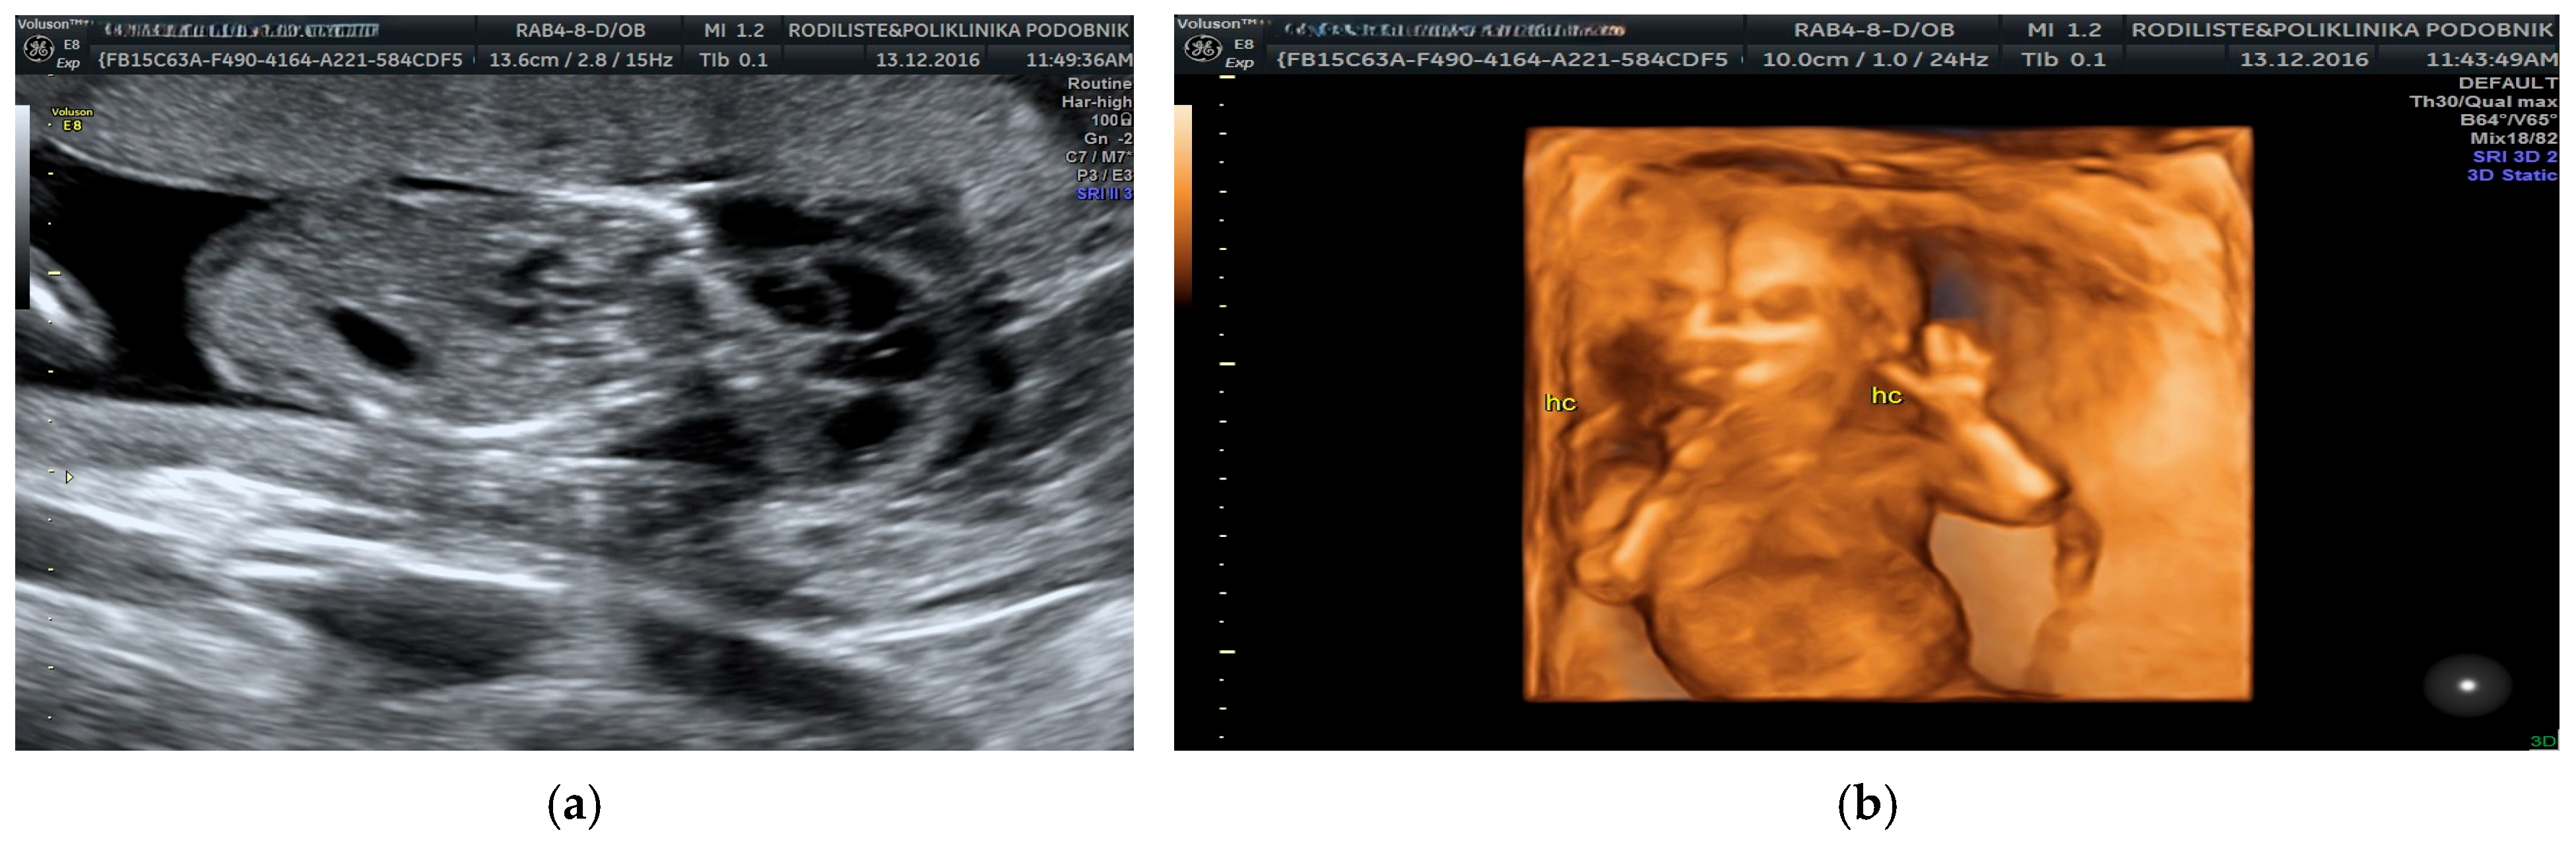

- Tsai, H.F.; Kang, L.; Tsai, P.Y.; Cheng, Y.C.; Yzu, C.H.; Chang, C. Prenatal diagnosis of fetal cystic hygroma using three-dimensional ultrasound in 2000–2011. J. Med. Ultrasound 2012, 20, 155–161. [Google Scholar] [CrossRef]